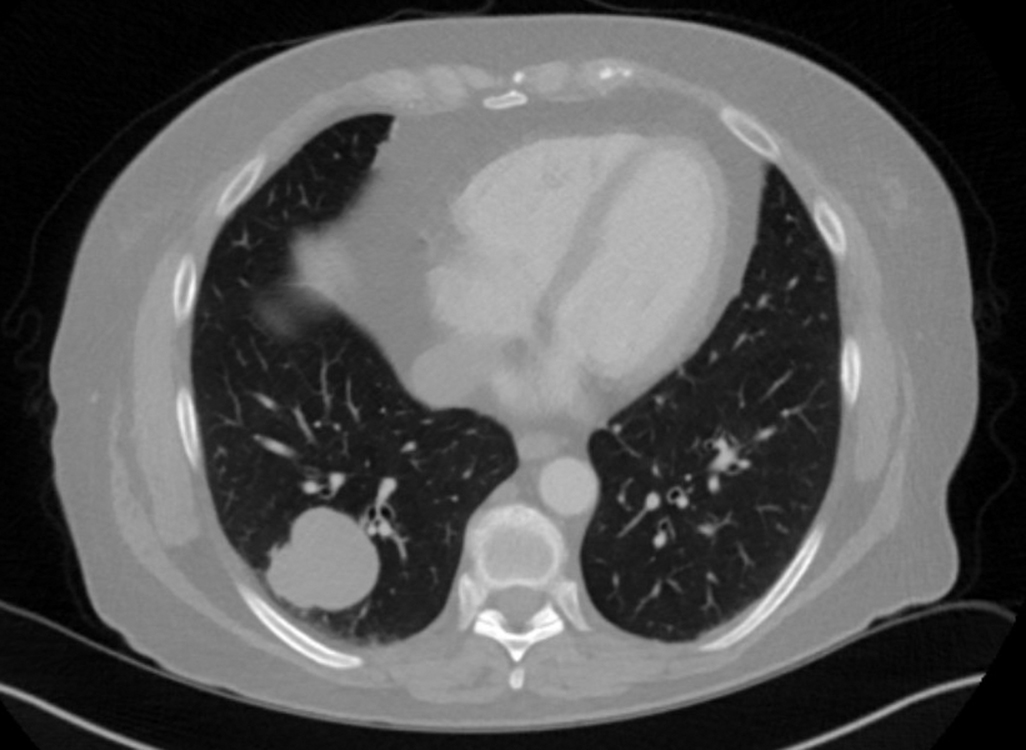

Figure 1 CT chest